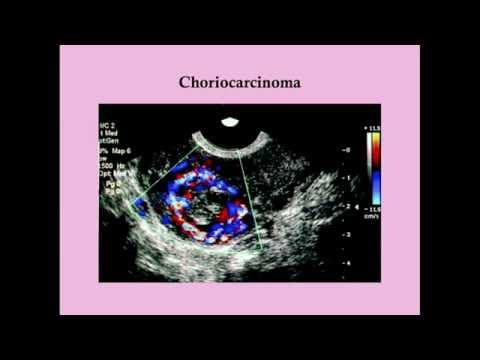

Ukoliko osim molarne degeneracije korionskih resica dolazi i do anaplastičnih promjena trofoblastnih stanica koje poprimaju karcinomatozne, maligne odlike govorimo o koriokarcinomu. Pri tome se kod koriokarcinoma, za razliku od molarne trudnoće ili korioadenoma, više ne mogu izdiferencirati korionske resice.

Točna patogeneza koriokarcinoma nije u potpunosti objašnjena ili shvaćena, ali studije su pokazale da citotrofoblastične stanice funkcioniraju kao matične stanice i da su podložne malignoj transformaciji. Neoplastični citotrofoblast dalje se diferencira u intermedijarni trofoblast i sinctiotrofoblast. Mješavina stanica oponaša normalan razvoj previloznog blastocista, što je obilježje i ostalih gestacijskih trofoblastičnih neoplazmi.

Otprilike u 50% slučajeva koriokarcinom se razvija iz kompletne hidatiformne mole. Maligna alteracija može nastupiti iz djelića trofoblasta zadržanih u maternici ili gdje drugdje. Ipak rizik nastanka koriokarcinoma iz mole hydatiformis leži oko 3 - 7%. U ovim slučajevima pretpostavlja se maligna alteracija i transformacija degenerativno promijenjenih trofoblastnih stanica. Nastanak koriokarcinoma iz parcijalne mole je izuzetno rijedak, iako i ovdje postoji realna, veoma niska mogućnost maligne transformacije. Koriokarcinom se međutim može razviti i iz sasvim normalnog tkiva posteljica. Procjenjuje se da 30% koriokarcinoma nastaje iz tkiva postljice zadržanog u maternici nakon spontanog pobačaja. Rizik nastanka koriokarcinoma raste s brojem spontanih pobačaja.